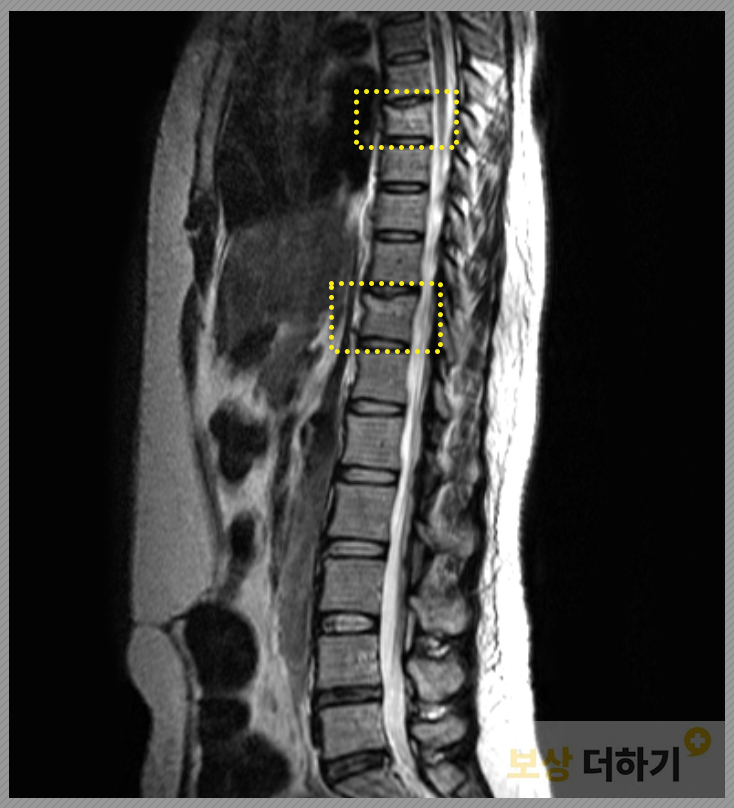

흉추 7번, 11번 골절 s22050 / s22070

척추 중에서도 등뼈에 부상을 입으셨고, 흉추 7번과 11번이 골절되었다는 결과가 나왔습니다. 이에 대해 8주 진단을 받으시고 비수술 치료가 시행되었습니다.